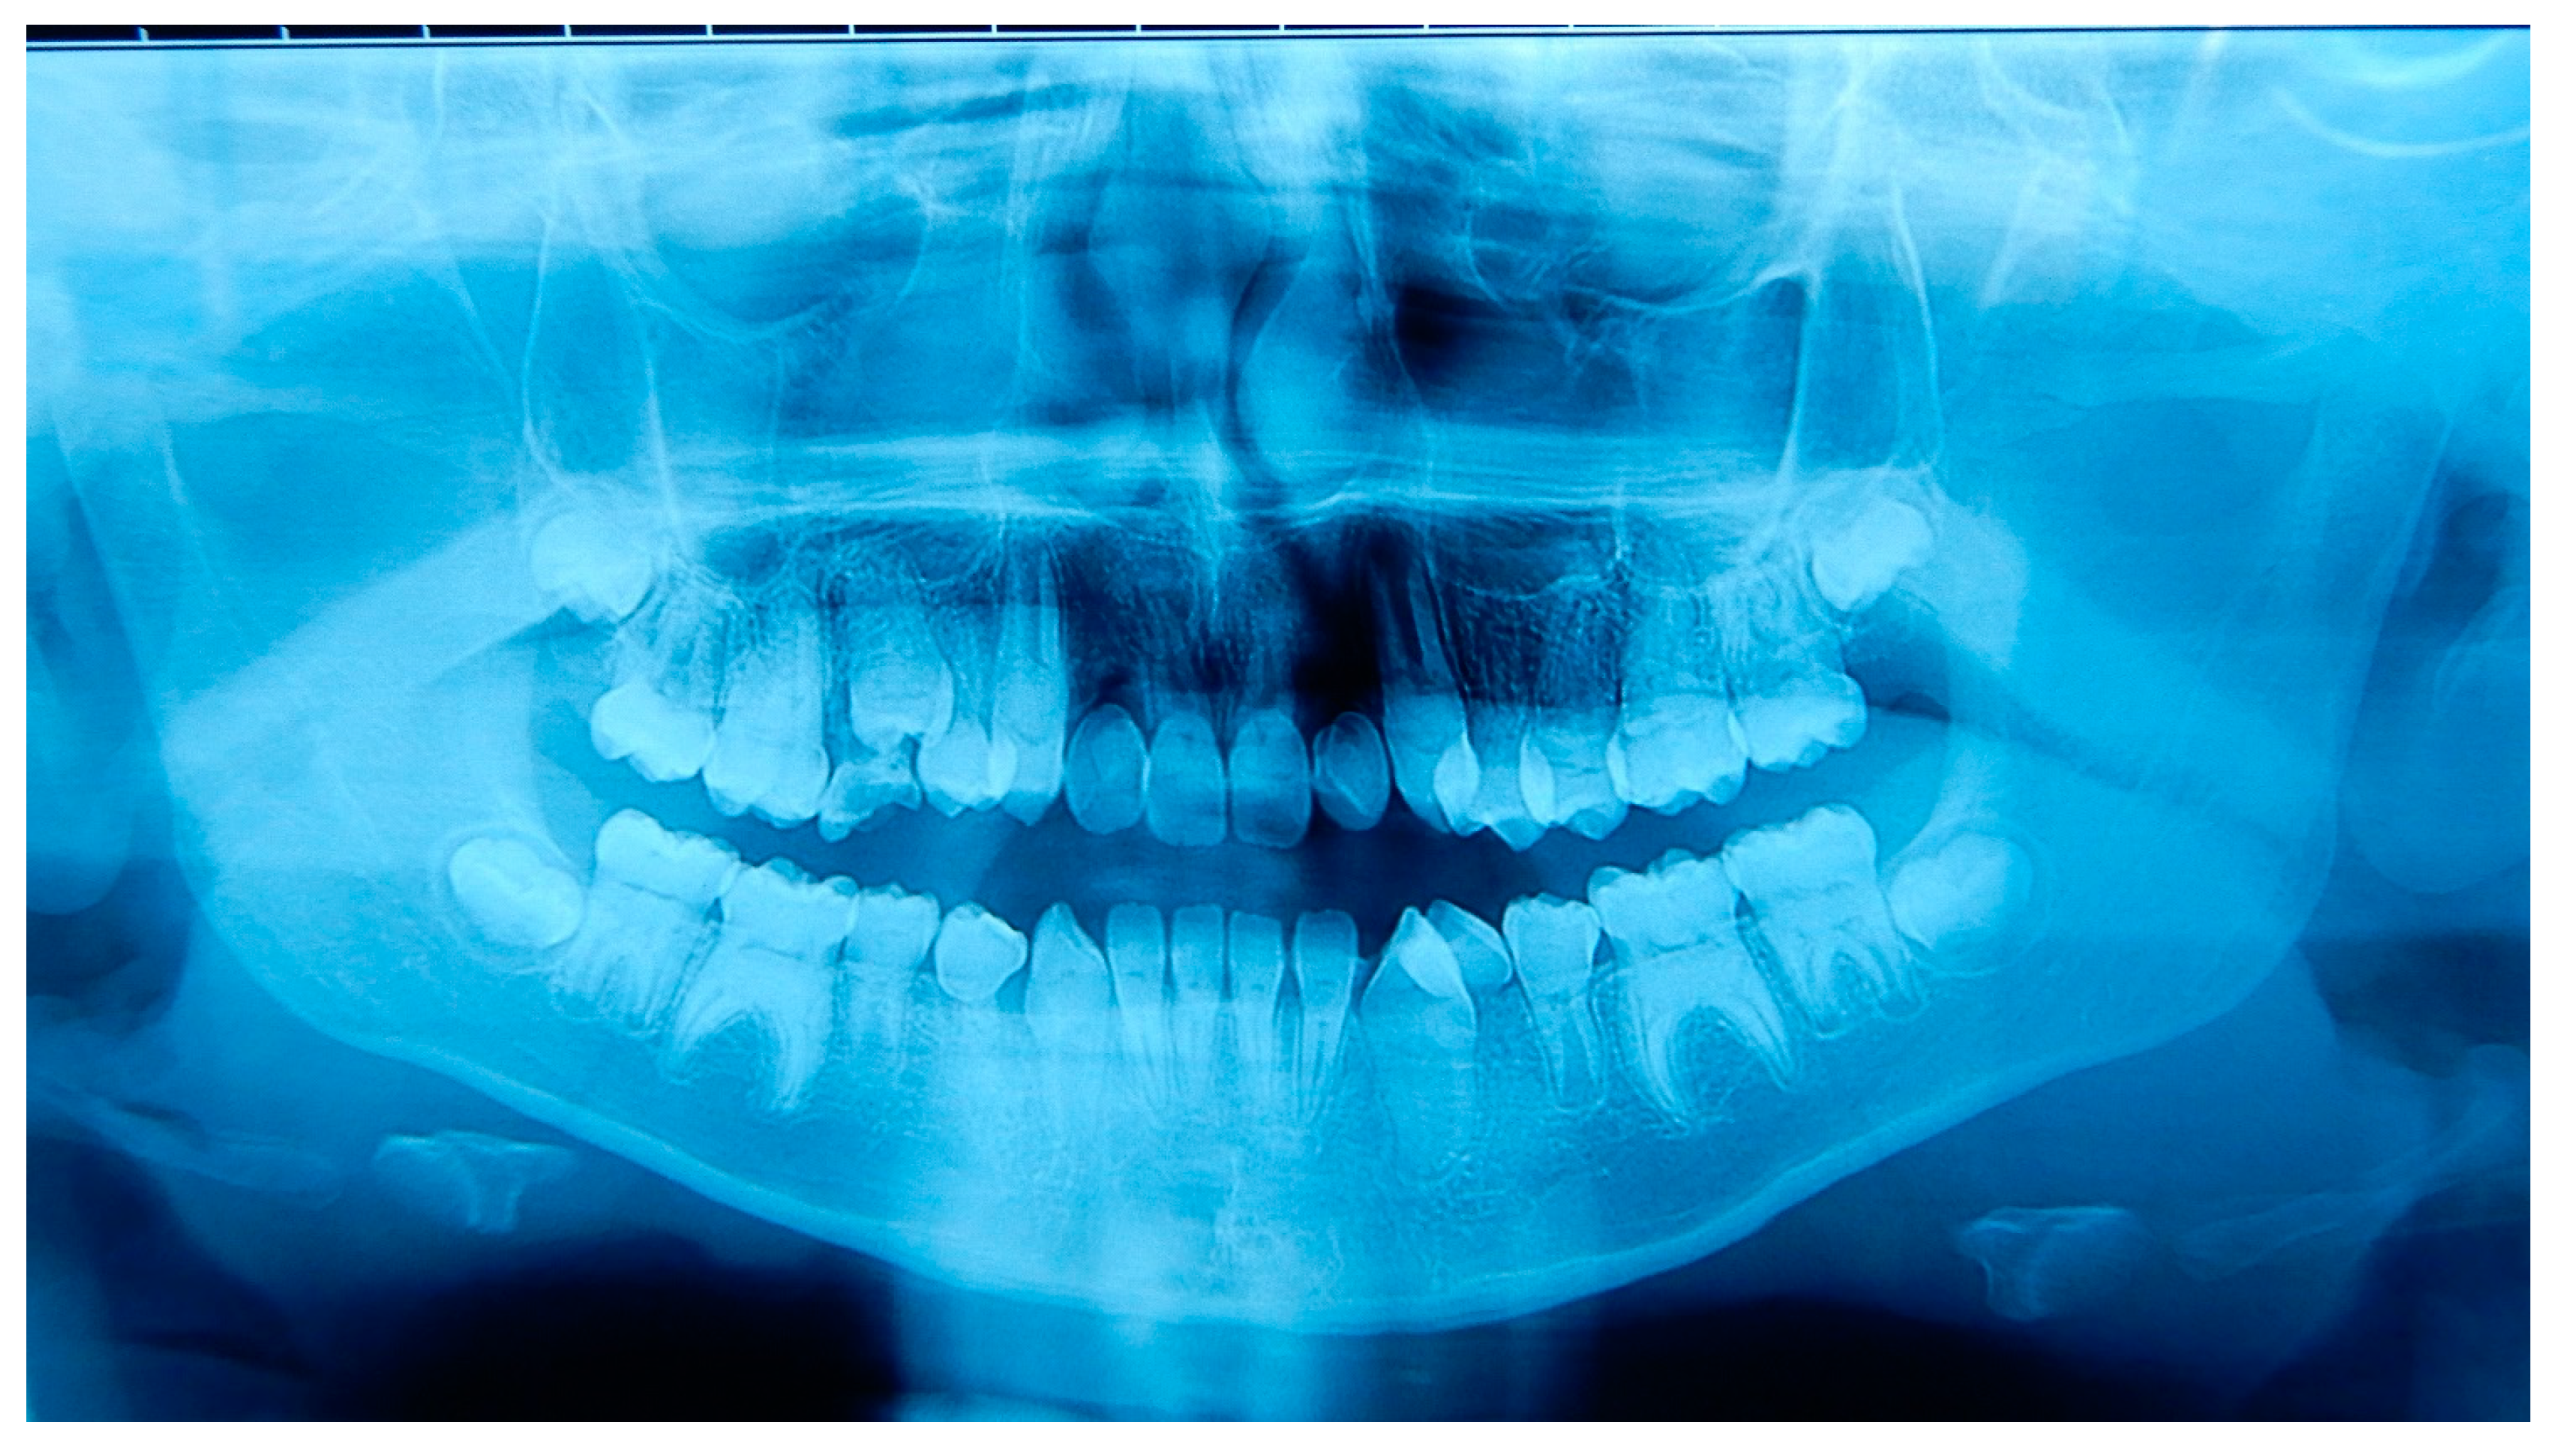

2.1. Patient A

2.2. Patient B

2.3. Father